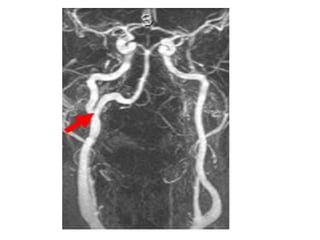

Left-sided PICA infarction , notice the posterior extension , the

infarction was the result of a dissection (blue arrow)

Left sided PICA infarction, in unilateral infarcts there is always a sharp delineation in the midline

because the superior vermian branches do not cross the midline but have a sagittal course, this

sharp delineation may not be evident until the late phase of infarction, in the early phase, edema

may cross the midline and create diagnostic difficulties, infarctions at pontine level are usually

paramedian and sharply defined because the branches of the basilar artery have a sagittal

course and do not cross the midline, bilateral infarcts are rarely observed because these

patients do not survive long enough to be studied but sometimes small bilateral infarcts can

be seen